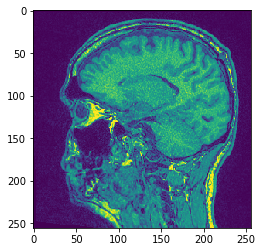

# Alternatively, don't hand over the output image and retrieve it

another_slice = cle.create_2d_xy(input_image)

cle.copy_slice(input_image, another_slice, slice_index = 80)

# show result

cle.imshow(another_slice)

../_images/94d2e1e1937c5fe79debe6f4cc905a8a4f9415fbce9ee61f1b66bdc05012264b.png